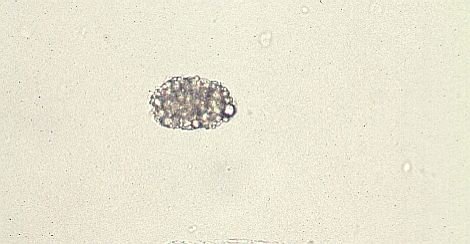

卵円形脂肪体

無染色

ズダンV染色

脂肪が橙色に染色される。